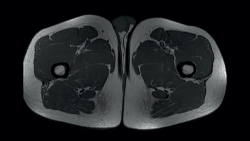

The femoral quadriceps is traditionally considered to be composed of four muscles: the rectus femoris (RF), vastus medialis (VM), vastus lateralis or externus (VE) and the vastus intermedius. However, a number of recent anatomical studies have described different variants of normal, with individuals presenting from 5 to 8 muscle heads(7). Of these, the RF is the only biarticular muscle; thus, in addition to conforming the primary flexor muscle group of the hip, it also extends the knee joint and is exposed to a risk of elevated elongation if movements of both are combined. Due to this characteristic, its length, tendency to perform eccentric-type contractions, and its high percentage of type II fast-twitch fibres, the RF is the quadriceps component most often affected by injuries. Mention also must be made of its complex proximal origin(8), with a direct tendon originating in the anterior inferior iliac spine and a second indirect (or reflected) tendon that originates in the supra-acetabular groove (Figure 2). At approximately 2 cm below their origin, both tendons form a combined tendon structure. The direct portion mainly contributes to the superficial component of the combined tendon and merges with the anterior aponeurosis or fascia of the muscle. In contrast, the indirect portion contributes to the fibres of the deep intramuscular component of the combined tendon and forms a deep musculotendinous junction that extends distally, approximately encompassing the two proximal thirds of the length of the muscle belly of the RF. This deep intramuscular tendon is initially located medially and is "comma" shaped (Figure 3). Distally, the tendon flattens out and becomes linear in shape with a sagittal long axis, and is located more laterally within the muscle(9). This central tendon (also called central aponeurosis or intramuscular septum) in turn gives rise to the muscle fibres that confer the bipennate appearance of this muscle. In turn, the direct tendon gives rise to a superficial expansion that anteriorly covers the proximal part of the muscle, from which muscle fibres also emerge. All the muscle fibres insert in the posterior aponeurotic expansion (posterior fascia) located on the dorsal surface of the muscle, which distally forms the anterior layer of the quadriceps tendon. In this way we have a bipennate structure originating from the central tendon, which differs from another surrounding structure originating from the superficial expansion and which is unipennate. This type of configuration has been referred to as a "muscle within a muscle"(10).

Figure 3. Axial (T1) view of the thighs, showing the typical "comma" image of the rectus femoris of both quadriceps.